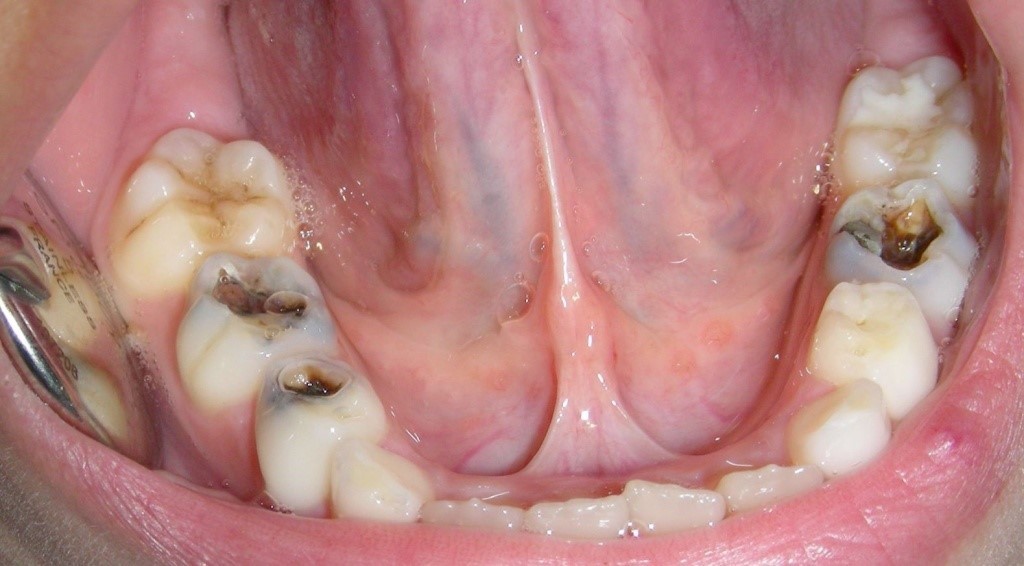

Seguramente hayas escuchado alguna vez que las caries en los dientes de leche no hay que darles demasiada importancia, ya que como estos se van a caer y nacer unos nuevos, pues que no es necesario realizar ningún tratamiento, pues bien, esto es totalmente falso y aquí te voy a explicar las consecuencias. Esta es la boca de un niño pequeño, fijaos que tiene prácticamente todos los dientes con caries, pero ¿por qué ocurren las caries con tanta facilidad en los dientes de leche? Los dientes de leche tienen una capa de esmalte más fina que la de los dientes definitivos, por eso las caries en los dientes de leche pueden avanzar más rápidamente que en las de los definitivos. Las caries, además del propio dolor que suelen generar si no se tratan pueden terminar por hacer que la pieza se pierda, como esta que estáis viendo aquí, lo que puede producir graves problemas en la forma de mordida del niño. Cuando un diente de leche se pierde de forma prematura se puede producir que los dientes de al lado se muevan impidiendo que el diente definitivo salga en su posición normal. Asi que cuidad la salud dental de los más pequeños.